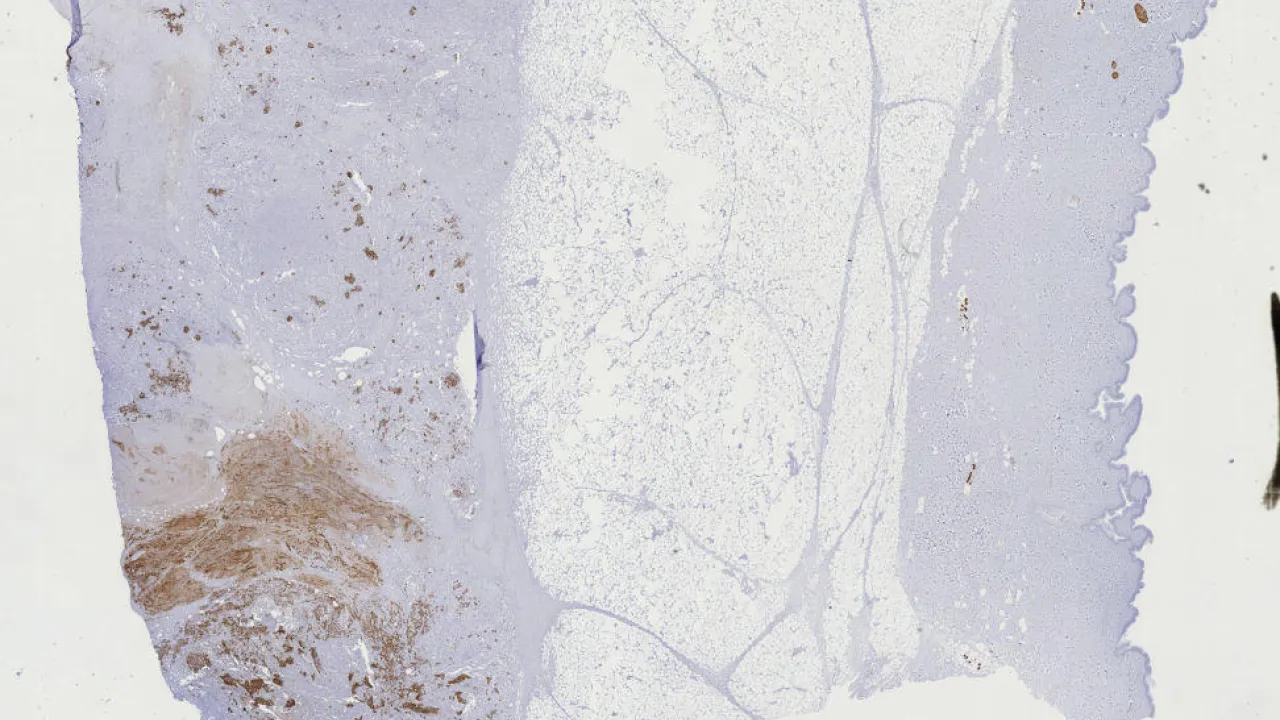

Lymph Nodes, Mixed phenotype acute leukemia, MPO stain